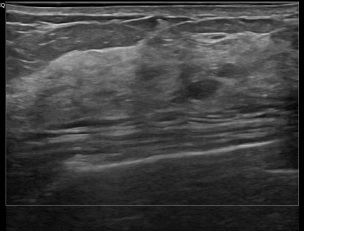

상기환자는 외부건진이상소견 정밀검사위해 내원하신 50대 초반

여성분으로 의심스러운 우측혹 조직검사 시행해 유방암 진단되었습니다.